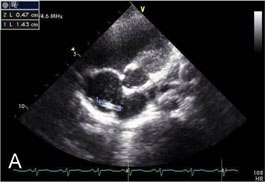

Fig. 1-B

TIVD inserted through Rt. SCV before a removal operation

Fig. 1-B TIVD inserted through Rt. SCV before a removal operation